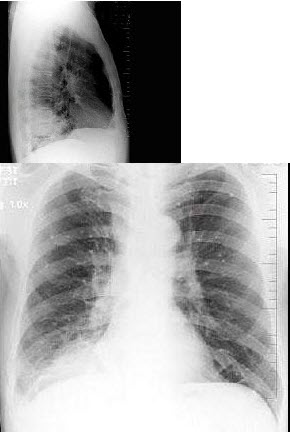

172、单项选择题

男,62岁,咳嗽、胸痛1月余,X线检查如图,最可能的诊断是()

A.右下肺炎症

B.右下肺不张

C.右肺癌

D.右肺转移瘤

E.右肺错构瘤

点击查看答案